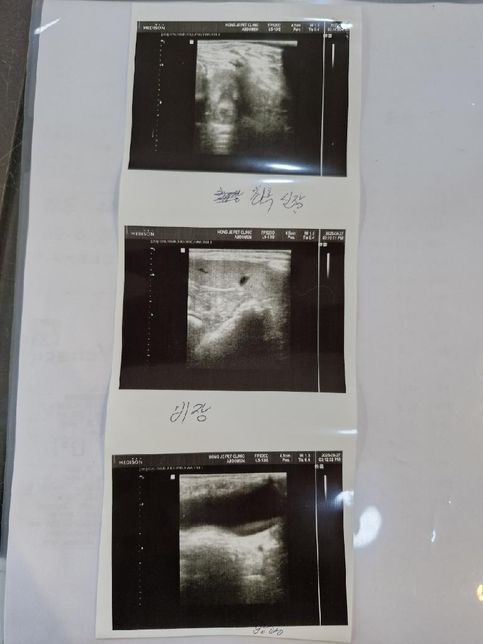

- 반려동물 건강반려동물Q. 어릴때 중성화 완료한 11살 수컷 전립선비대가 있습니다 전립선 그리고 방광 그리고 담낭좀 봐주시면 감사하겠습니다.현재 거의 포피염이 작년 9월경부터 낫지를 않고 있습니다.초음파는 예전에도 수차례 찍었지만 어떻게 우연히 전립선비대를 발견하게됬습니다.질문1) 전립선염이 있는지 방광염이 있는지 항생제를 먹어야할지 알려주세요.질문2) 담낭슬러지 우루사 어느정도 먹여야할정도인지.. (혈액검사상 담즙 흐름은 원활하다 합니다)단 한번도 우루사를 먹여 본적이 없습니다 질문3) 신장결석이 어느정도인지.. 알려주세요사진 순서대로 전립선 우측부신 좌측 신장 비장 방광 순입니다.